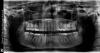

IvanK Опубликовано 4 сентября, 2013 Поделиться Опубликовано 4 сентября, 2013 Дык, как же я контактную поверхность между зубами-то сфотографирую?Выложите панорамный снимок (ОПТГ) Ссылка на комментарий

lida1506 Опубликовано 4 сентября, 2013 Автор Поделиться Опубликовано 4 сентября, 2013 (изменено) Выложите панорамный снимок (ОПТГ) Изменено 4 сентября, 2013 пользователем lida1506 Ссылка на комментарий